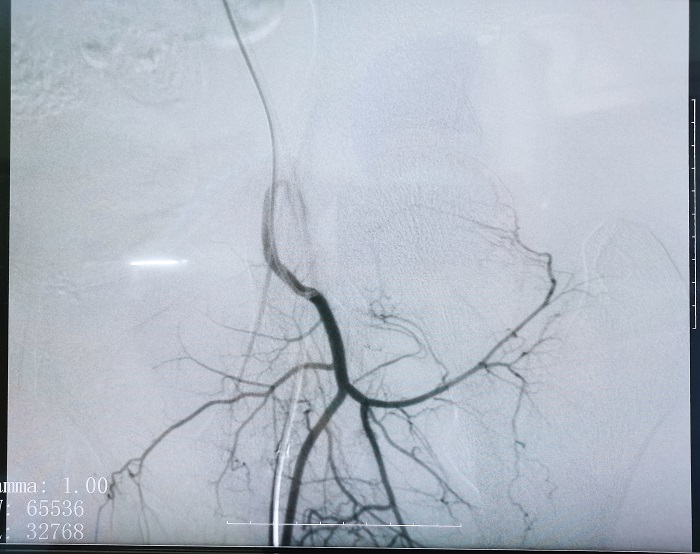

普愛平板介入中C在FTE手術過程中拍攝的造影圖像

若根據(jù)HSG的診斷,患者存在輸卵管積水,則可行輸卵管栓塞術(Fallopian tube embolization, FTE),通過介入手段,注入栓塞劑或使用彈簧圈等器材進行栓塞,可以有效地阻斷輸卵管內的血流和組織,從而治療輸卵管積水。這個過程通常是在X線或超聲引導下進行的,可以清楚地看到輸卵管的情況。